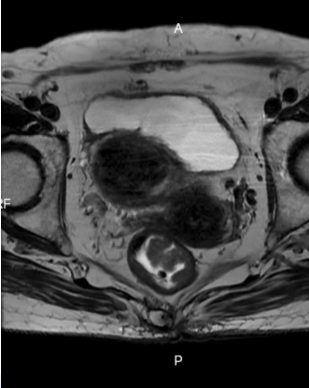

83岁的李老太因排便不畅10天来到青岛西海岸新区中医医院肛肠科门诊就诊。刘艳君副主任医师经肛门指诊发现距肛缘7cm处存在直径约3cm的肿物,初步判断风险后立即安排肠镜检查。

肠镜结果显示为直肠下段侧向发育型肿瘤,直径约3cm,环腔范围达1/2,病理虽提示良性管状腺瘤,但因体积较大不排除局部恶变。